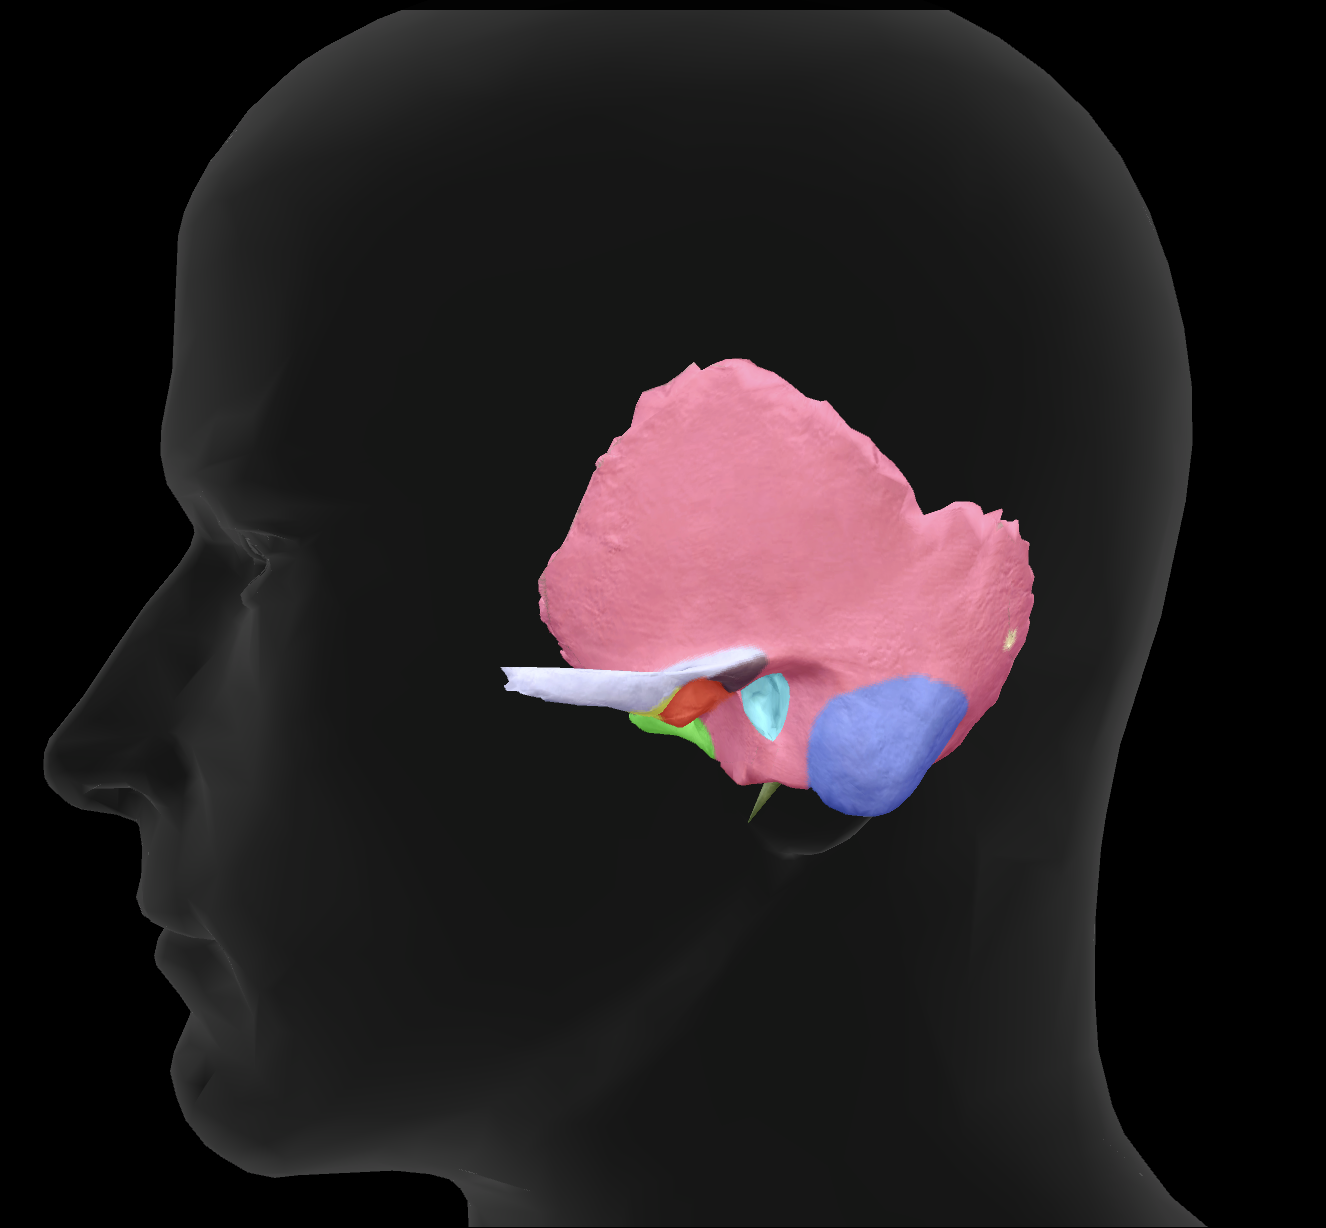

What bone is highlighted?

zygomatic bone

zygomatic process of temporal bone

What is the name of this feature?

external auditory meatus

What is the name of this feature?

mandibular fossa

What is the name of this feature?

mastoid process

What is the name of this feature?

styloid process

What connects to the zygomatic process to make the zygomatic arch?

temporal process of the zygomatic bone